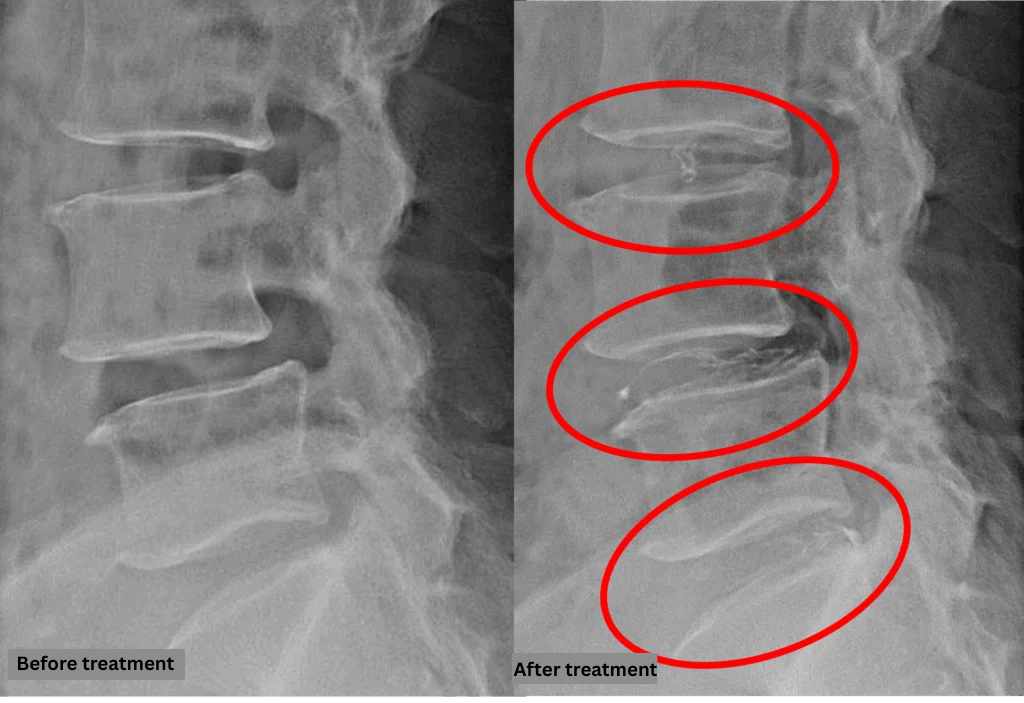

- L3/4, L5/S: Intervertebral disc degeneration and bulging

- L4/5: Intervertebral disc degeneration, bulging, degenerative spondylolisthesis

The above findings were also observed on the imaging.

Compression of the spinal canal caused by disc abnormalities at L3/4, L4/5, and L5/S was considered the most likely source of symptoms.

After consulting with the patient, the Cellgel Method was performed on 3/4, 4/5 and 5/s.